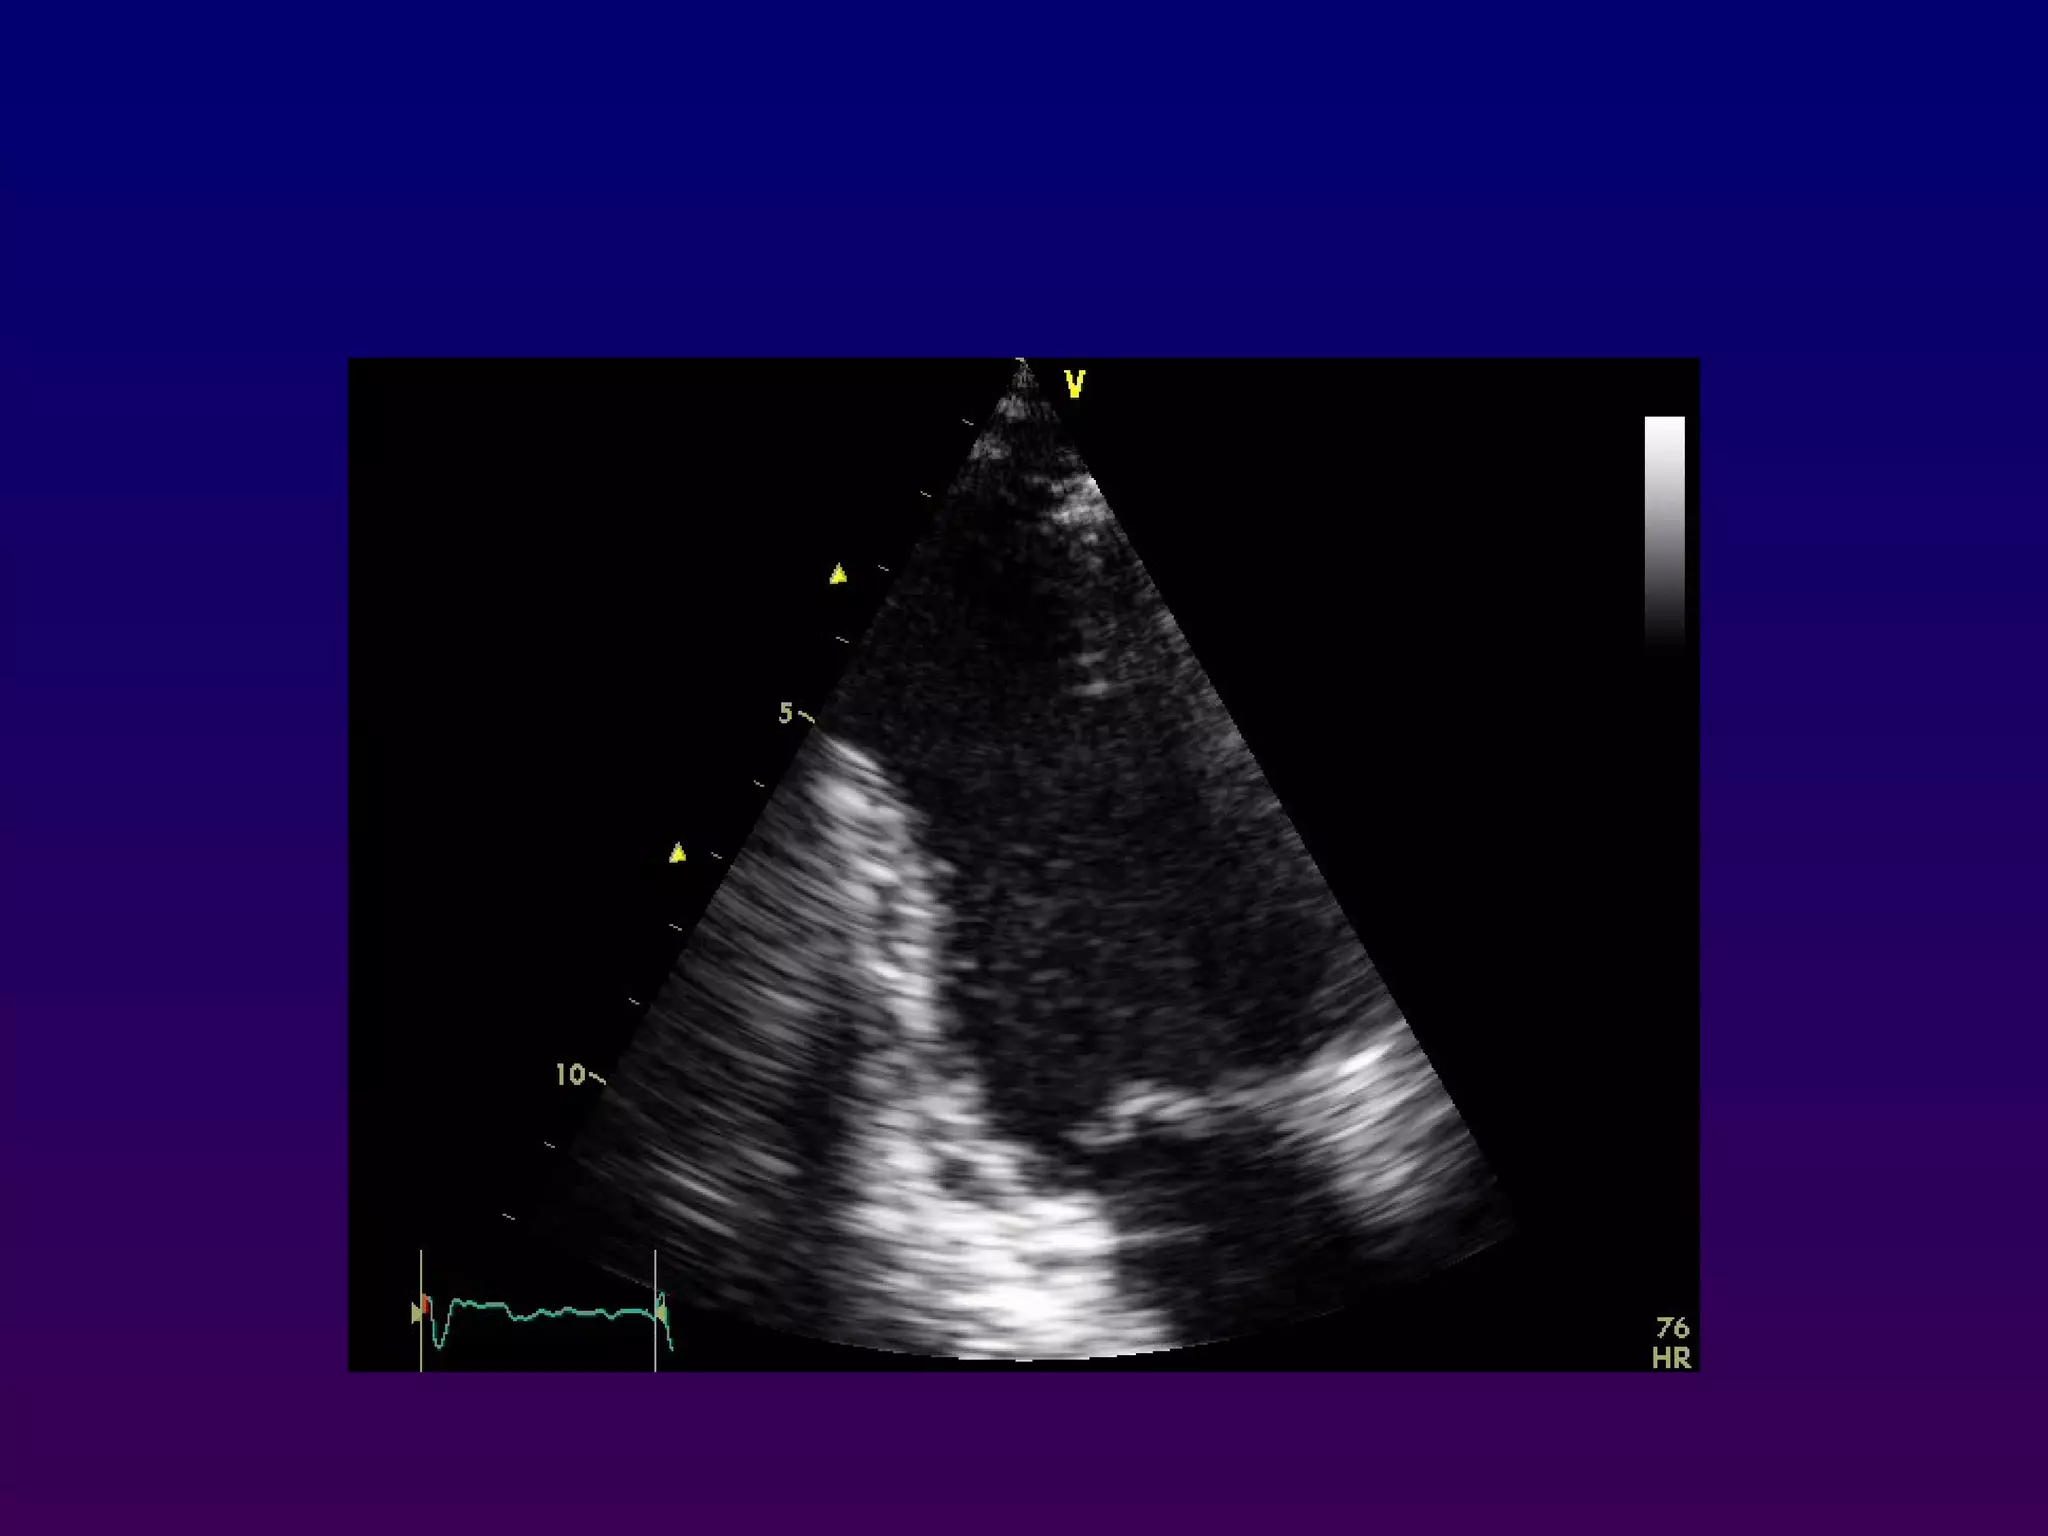

Right ventricular inflow and outflow

Inferomedial angulation from the parasternal long-axis

position is performed to obtain the "right ventricular

inflow" view which includes the right atrium,

coronary sinus, septal and anterior leaflets of the

tricuspid valve and basal right ventricle

Right ventricular inflowand outflow Inferomedial angulation from the parasternal long-axis position is performed to obtain the "right ventricular inflow" view which includes the right atrium, coronary sinus, septal and anterior leaflets of the tricuspid valve and basal right ventricle •Superior angulation of the probe permits depiction of the right ventricular outflow tract, including the pulmonic valve and main pulmonary artery. PVTV RA